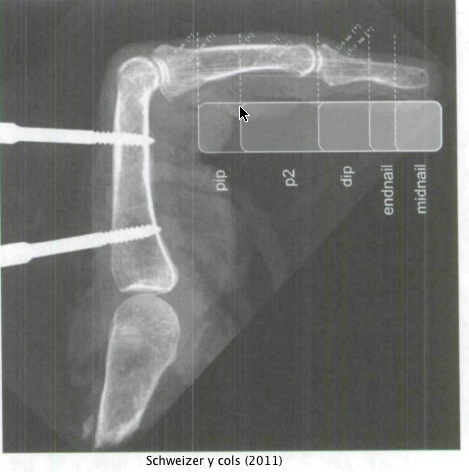

En un reciente estudio a cargo de Schweizer y cols (2011), estudiaron la fuerza que ejercen los tendones de los flexores en cinco diferentes tamaños de agarres, tanto en arqueo como en extensión. Para ello, valiendose de manos cadavéricas, tiraron de los dos tendones principales (de a uno y luego juntos) con 40N de fuerza y midieron la resultante de la misma fuerza a nivel del agarre.

En el arqueo sobre presas pequeñas el flexor común profundo de los dedos (es el tendón que va hasta la ultima falange) es el que mas fuerza ejerce, mientras en presas grandes es el flexor superficial (el que va hasta la anteúltima falange). En el caso del agarre en extensión el flexor profundo fue el principal en todos los casos.

Los autores concluyen que la preferencia de los escaladores a arquear no solo es porque pueden utilizar la ayuda del pulgar para ejercer mas fuerza, pero también al hecho de que en esta posición se puede generar una mayor fuerza de flexión y torque. Cuando se cargan ambos tendones (superficial y profundo), el arqueo siempre genera mayor momento de flexión con respecto a la posición en extensión independientemente del tamaño del agarre.